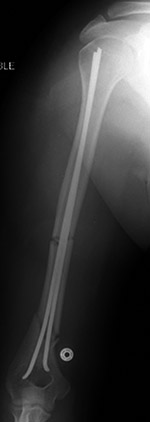

Intramedullary Nails/Rods

Intramedullary nailing was introduced by Gerhard Kuntscher (1900-1972) in 1940 and represented a revolution in the treatment of femoral shaft fractures. Since that time, the technique has evolved considerably (Ruedi, 2007; Benjamin, 1994; Wiss, 2013; Berquist, 1995; Freiberg, 2001; Hunter, 2001; Ajmal, 2001; Oh, 2002). Intramedullary nailing is the standard treatment for diaphyseal fractures of the femur and tibia (figure: intramedullary rods/nails; figure: antegrade intramedullary hip nail; figure: tibial intramedullary nail). Humeral shaft fractures are also being treated with antegrade and retrograde intramedullary nailing, with variable complication rates being reported (figure: humerus intramedullary nails). Intramedullary nails or rods allow early weight bearing and functional use of the extremity. The intramedullary location of the nails provides optimal biomechanical positioning to resist torsion and bending (Ajmal, 2001).

Nails typically traverse a fracture and are often used as a rigid support for screws, pins, or other nails or rods used to fixate a fracture (Orthopedic Hardware Atlas). In many radiology practices the terms rod and nail are used interchangeably. Radiologists seem to favor the term rod while orthopedists favor the term nail.

In a purist sense, rods are simple solid cylinders which are thinner and more flexible than nails. For the purposes of this discussion, the terms nail and rod will be used interchangeably, but one should realize local custom often determines medical device terminology. Nails/rods have proximal and distal holes for the insertion of locking (interlocking) screws and pins that stabilize the nail in the bone and prevent rotation of the distal portion of the fractured bone on the proximal portion. Nails can be solid or hollow and come in a variety of cross-sections from round to square to star shaped (Orthopedic Hardware Atlas).

Most intramedullary nailing is done closed with minimal soft-tissue exposure, either in an antegrade or retrograde fashion depending on the fracture site. Both antegrade and retrograde nailing are used for femoral and humeral shaft fractures, and for tibial shaft fractures antegrade nailing is used. The entrance site for an antegrade femoral nail is created in the piriformis fossa; for the retrograde femoral nail, in the intercondylar region; and for the antegrade tibial nail, anteriorly just below the joint line.

The nails are introduced over a guide wire, frequently after reaming with flexible reamers to enlarge the intramedullary canal. Because reaming causes temporary damage to the internal cortical blood supply, which is associated with increased infection rates, it is not recommended for the treatment of some open fractures. There is also an increased rate of pulmonary complications including pulmonary embolism with reaming; therefore, controversy persists between those who recommend reamed nailing and those who do not in severely traumatized patients. Intramedullary nailing is performed with intraoperative fluoroscopic guidance (Ruedi, 2007; Benjamin, 1994; Wiss, 2013; Berquist, 1995; Freiberg, 2001; Hunter, 2001; Ajmal, 2001; Oh, 2002).